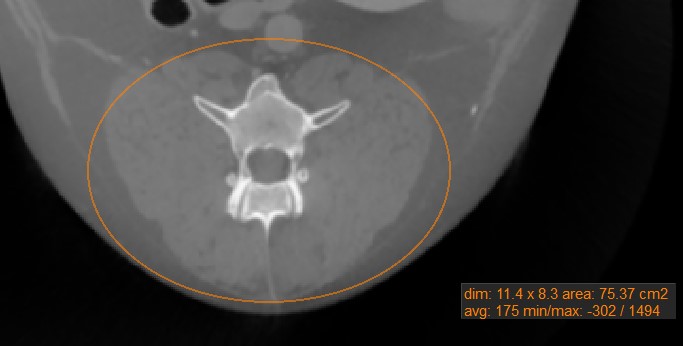

Oval¶

Wählen Sie das Werkzeug Oval aus und weisen Sie es einer der verfügbaren Maustasten zu. Starten Sie die Messung, indem Sie auf die aktive Bildschicht klicken und die Maus ziehen, um eine ovale Form zu erstellen. Lassen Sie die Maus los, wenn die Größe des markierten Bereichs zufriedenstellend ist.

Alle verfügbaren Messwerte werden zusammen mit der Messung angezeigt.

Ändern Sie den markierten Bereich, indem Sie einen der vier Punkte des um das Oval gezeichneten Rechtecks mit dem Werkzeug Standard verschieben.